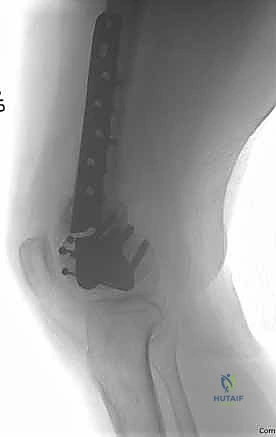

"Now, let's consider the most challenging scenario: a fracture-dislocation of the olecranon. These injuries often involve the coronoid process, radial head, and collateral ligaments. Our approach needs to be comprehensive."

Image

TECH FIG 4 • A. A complex anterior fracture-dislocation of the elbow. A lateral radiograph shows extensive comminution of the trochlear notch of the ulna, including the coronoid, and anterior displacement of the forearm. B,C. The coronoid fragments are connected to the dorsal metaphyseal fragments in this patient, which facilitates reduction and fixation. ( A,C: Copyright David Ring, MD.)